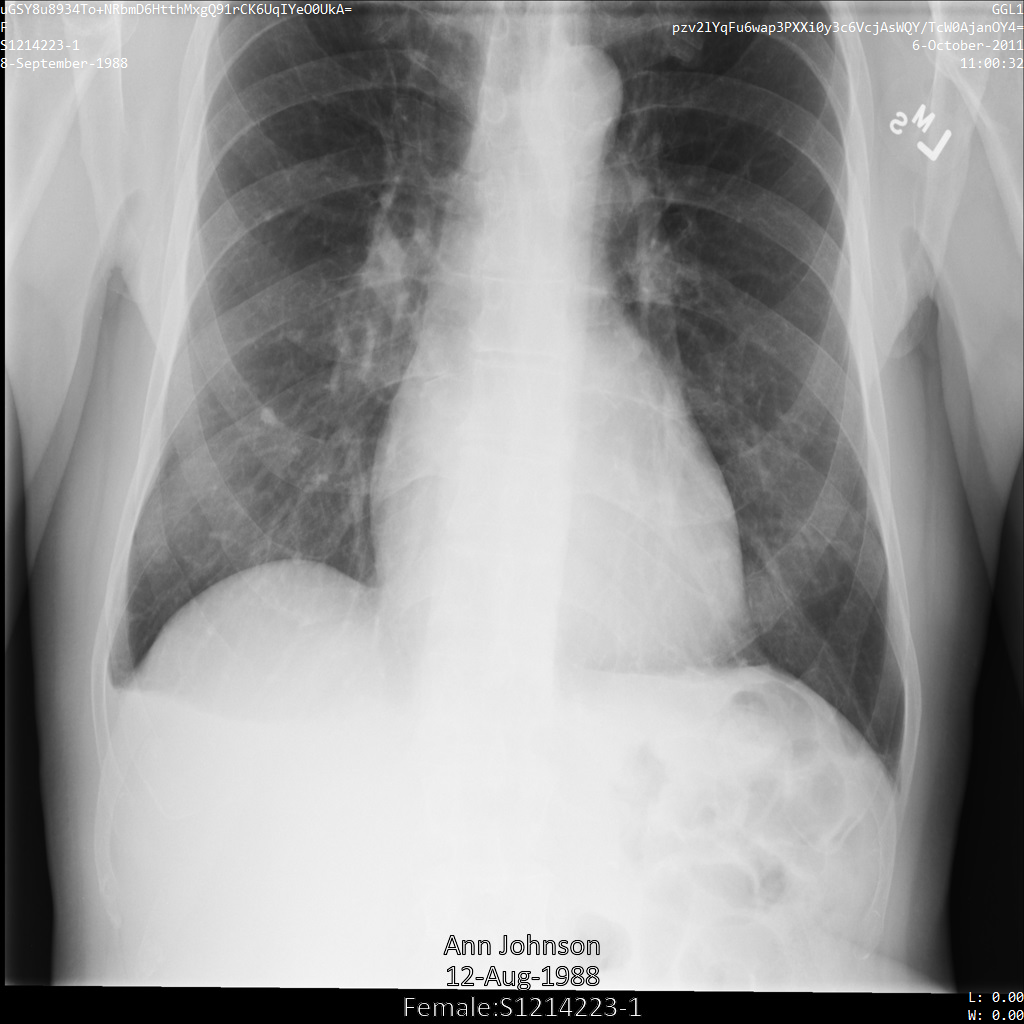

以下の各セクションでは、DICOM データを匿名化するさまざまな方法について、例を示しています。また、それぞれの例で匿名化された出力画像を示しています。各例では、入力として以下の元画像を使用しています。

各匿名化オペレーションからの出力イメージをこの元のイメージと比較して、オペレーションの効果を確認できます。

Cloud Healthcare API に画像を送信すると、画像は次のように表示されます。画像の上部隅に表示されているメタデータは削除されていますが、画像の下部にある焼き付き保護対象保健情報(PHI)は残ります。焼き付きテキストも削除するには、画像の焼き付きテキストを削除するをご覧ください。